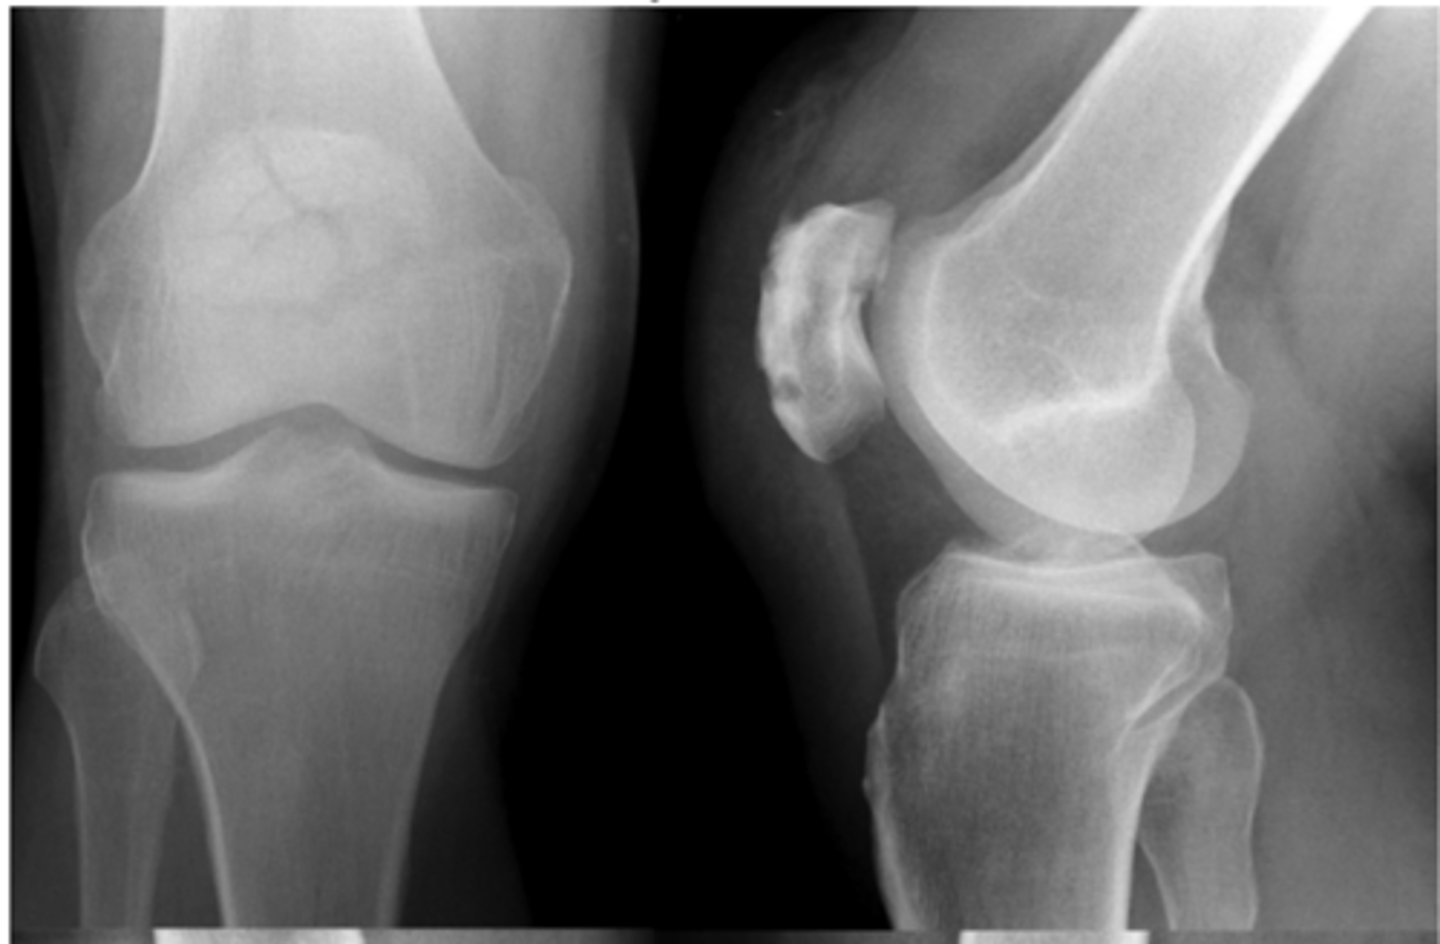

Grade I = minimal osteophytes w/ no problems w/ space or cartilage

Define the Kelgren Lawrence grade. How do you know?

Grade II = 1 definite osteophyte w/ NO space narrowing

Grade III = marginal osteophytes w/ space narrowing + sclerosis & multiple osteophytes

Grade IV = obliteration of joint space (bone on bone)